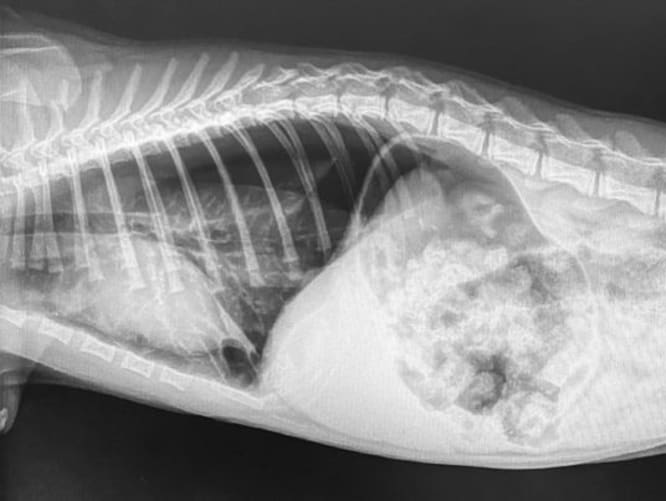

Mukki hat mehrere Verletzungen

Er braucht Operationen und muss unter Aufsicht sein. Um ihm diese zu ermöglichen brauchen wir deine Unterstützung.